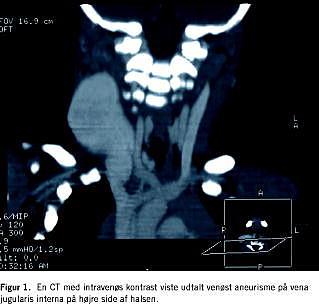

Der blev foretaget en ultralydskanning med Doppler, hvilket viste en hypoekkoisk tumor med flow. Der blev aspireret fra tumoren med finnål, og aspiratet viste venøst blod. En CT med intravenøs kontrast viste udtalt venøst aneurisme på vena jugularis interna på højre side (Figur 1 ). Der fandtes normalt kalibrerede kar under foramen jugulare. Aneurismet begyndte 2 cm distalt herfor og strakte sig ned i apertura thoracis superior, hvor vena jugularis interna igen antog normal kaliber. Resten af halsen var normal.